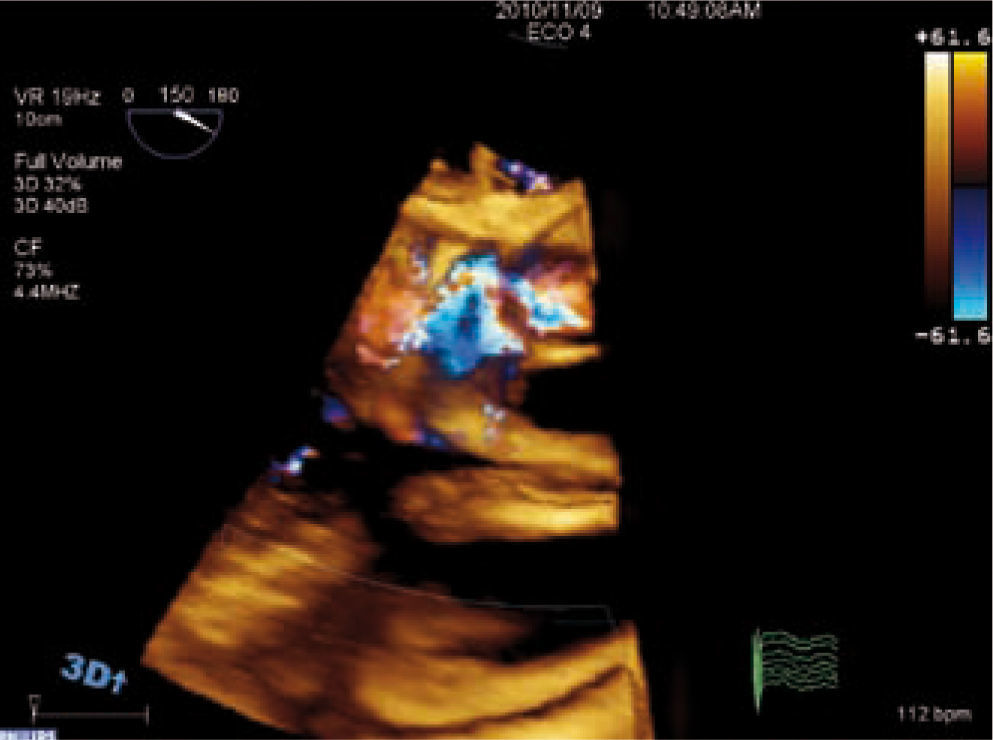

DiagnósticoEl ecocardiograma es la técnica de elección para el diagnóstico de la valvulopatía aórtica, ya que permite valorar anatómicamente la válvula, determinar su gravedad y ver la repercusión hemodinámica sobre el ventrículo izquierdo (VI) de forma rápida, segura y reproducible3. El ecocardiograma transesofágico (ETE) puede ser útil en casos dudosos, ya que permite medir el área valvular siempre que la válvula no esté muy calcificada. Con las nuevas tecnologías podemos valorar la válvula aórtica por ecocardiograma tridimensional, lo que nos aporta más información acerca de su anatomía y gravedad de la estenosis, podemos obtener la válvula en tres planos ortogonales y medir con mayor precisión el área valvular como se muestra en la figura 1.

Para diagnosticar una EAo grave debemos aportar tanto el área valvular como medidas de flujo, entre éstas la más validada es el gradiente medio. Una EAo es grave cuando el área valvular es menor de 1cm2 y el gradiente medio transvalvular es mayor de 40mmHg, como se esquematiza en la tabla I. Las mediciones que realizamos habitualmente en la valoración cuantitativa de la EAo se muestran en las figuras 2–5. El ETE 3D es fundamental en la medición del tracto de salida del VI (TSVI) previo al implante de una prótesis por vía percutánea (Fig. 6), además de para guiar estos procedimientos.